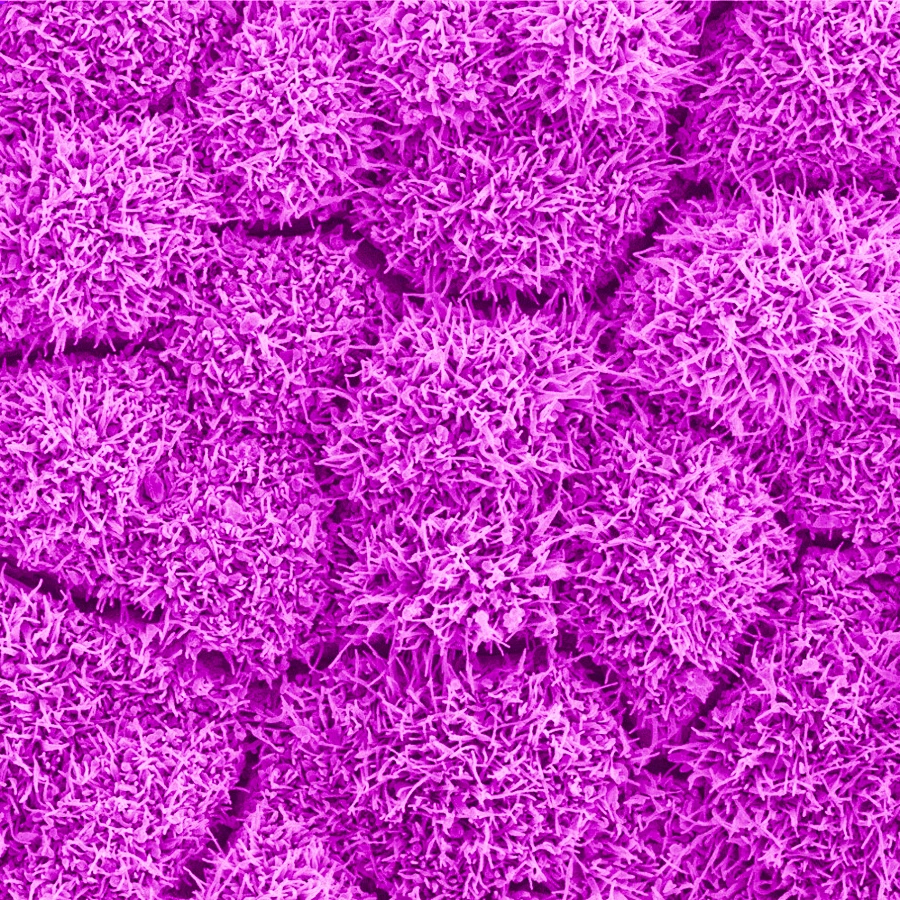

This mat of fluffy pink cells is the retinal pigment epithelium (RPE), a layer of cells that separates other cells in the retina from layers of blood vessels and connective tissue, forming a protective barrier.

In this image we are looking down on the cells of the retinal pigment epithelium. Individual cells (1) are distinguished by the small fissures (2) that run through the image. Researchers at the National Eye Institute used AI to refine this image, increasing the speed at which the image was captured as well as the image contrast.

RPE cell bodies are typically about 14 micrometers across, roughly 5 times smaller than the width of a human hair.

These images were created using confocal microscopy.